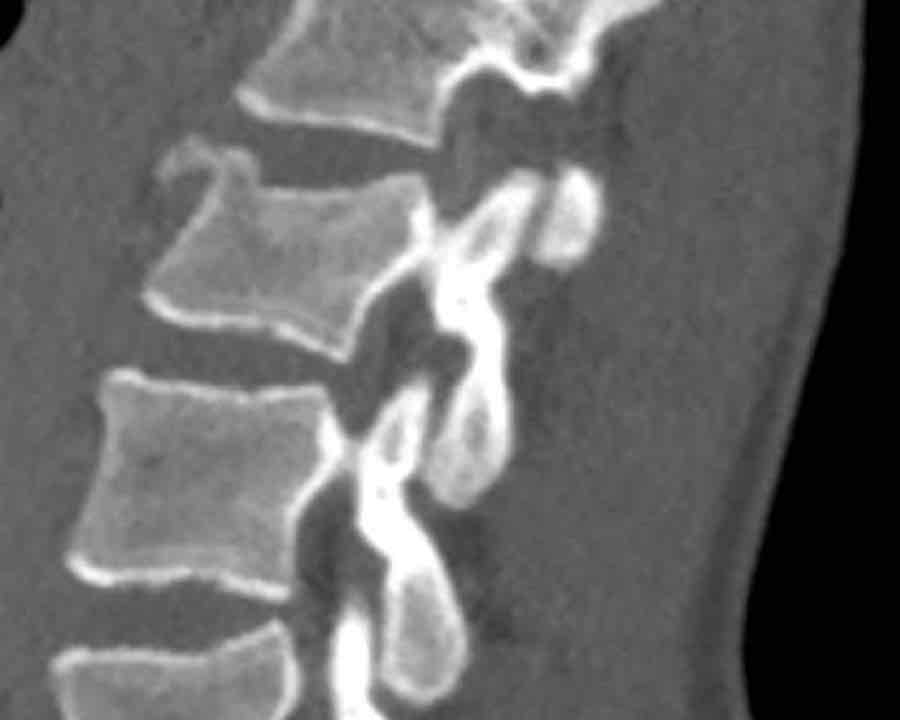

What is the AO-type of the vertebral body fracture based on only these two inages?

Findings:

- Fractures of the vertebral body with involvement of upper endplates (1 points) and posterior wall (2 points)

- Bulging of the posterior wall without any other signs of dislocation is the result of the burst fracture.

Therefore no C injury.

Conclusion

Injury type A3